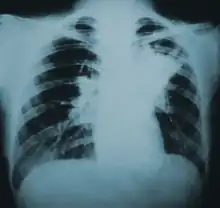

Lung infiltration in blastomycosis.